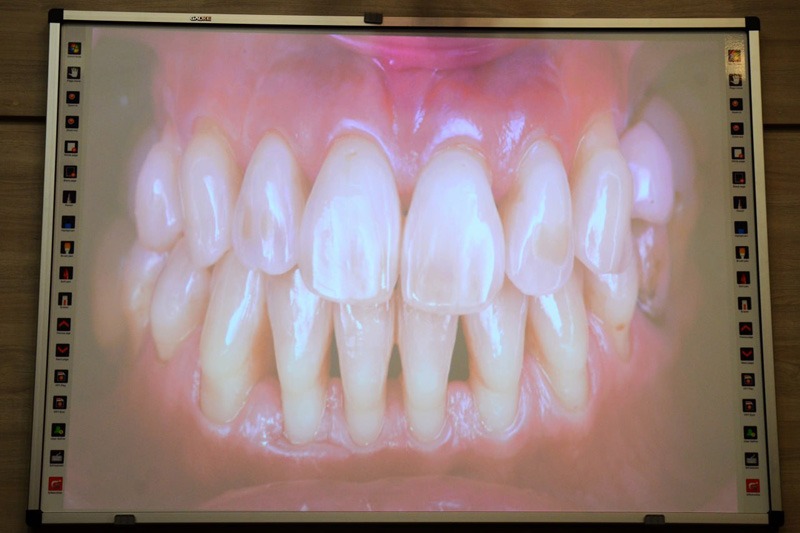

Спікером лекції виступив Мирослав Солонько – PhD (Іспанія), MBA (Іспанія), сертифікований спеціаліст Європейської федерації пародонтологів, президент ГО «Українська асоціація пародонтології та остеоінтеграції». У своїй доповіді він детально розглянув трансформацію ролі пародонтології в епоху імплантації, а також окреслив ключові фактори, що впливають на прийняття клінічних рішень.

- як змінилися пріоритети в лікуванні пацієнтів із пародонтологічними захворюваннями;

- які клінічні фактори визначають вибір між збереженням зуба та імплантацією;

- які сучасні наукові дані свідчать про довгострокові результати лікування;

- які стратегії дозволяють зберігати стратегічно важливі зуби.